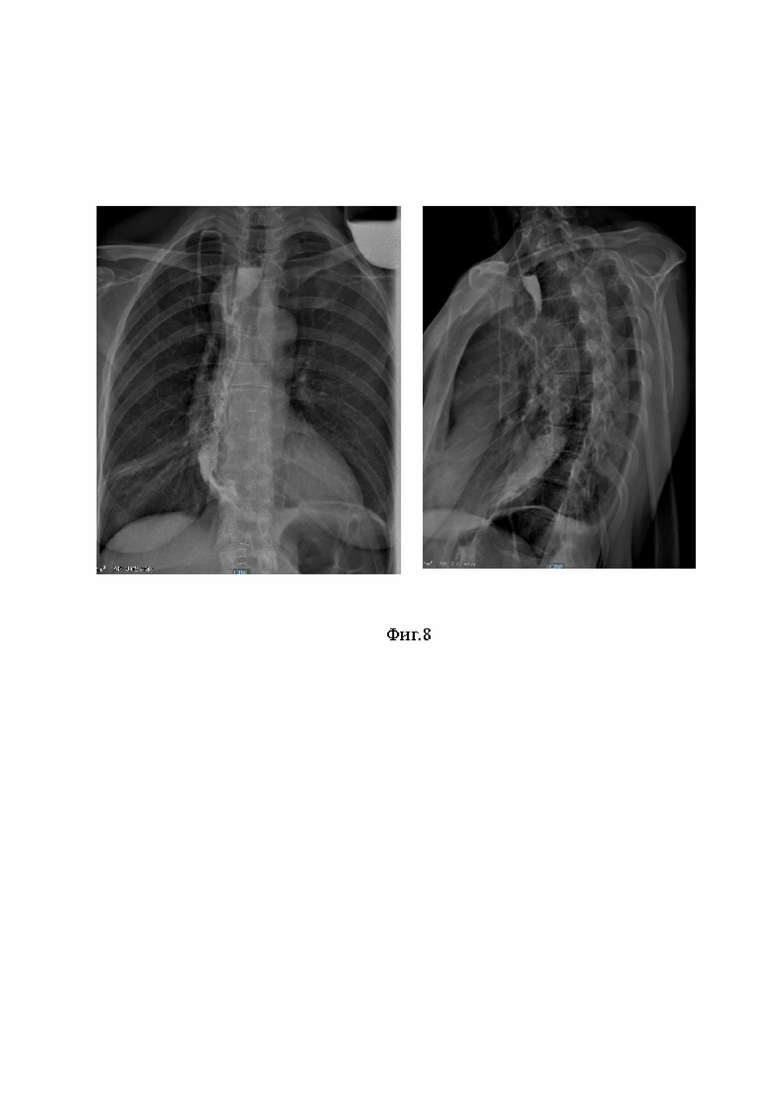

На фигурах 7 и 8 представлены фотографии, иллюстрирующие приведенные клинические случаи.

Пример 2.

Пациентка X, 58 лет. Госпитализирована в хирургическое торакальное отделение с диагнозом: Гастроинтестинальная стромальная опухоль среднегрудного отдела пищевода T2N0M0, I стадия. Онкологическим консилиум решено провести оперативное лечение в объеме резекции пищевода по Льюису. 06.02.24 выполнена резекция пищевода по Льюису гибридным доступом (лапаротомия + торакоскопия справа). На абдоминальном этапе операции мобилизован желудок, сформирован желудочный кондуит. На торакальном этапе обеспечен однопортовый доступ в правую плевральную полость, выделен и резецирован пищевод с опухолью. Далее сформирован пищеводно-желудочный анастомоз в куполе плевральной полости между желудочным кондуитом и верхней третью пищевода заявляемым способом. Послеоперационный период протекал гладко, без осложнений. Пациентка провела сутки в реанимации, после чего переведена в отделение торакальной хирургии. На 2-е сутки послеоперационного периода пациентке разрешено пить воду 5 мл в минуту. На 5-е сутки проведена контрольная рентгеноскопия пищевода с водорастворимым контрастом - пищевод проходим, затеков контрастного вещества не выявлено. Диета расширена до 1а стола. Пациентка выписан на 9-е сутки в удовлетворительном состоянии.

На фигуре 8 приведены фотоизображения рентгеноскопии пищевода с водорастворимым контрастом, слева - фронтальная проекция, справа - левая боковая проекция.